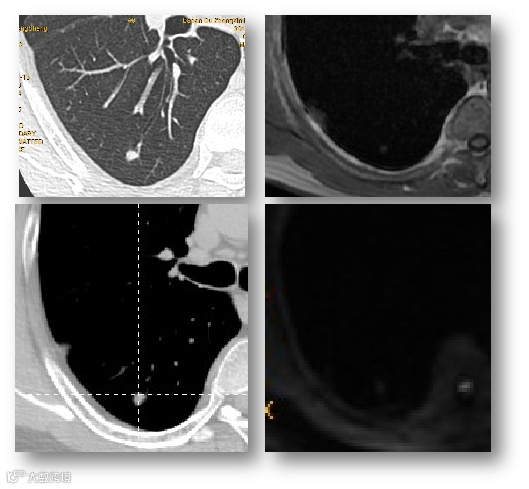

AI初筛+医生复核:AI标记可疑结节,医生重点分析,效率与准确性双提升。

动态随访系统:AI自动对比历史影像,预警结节生长趋势,医生决策更从容。

多模态学习:融合CT、PET、液体活检等多维度数据,让诊断更立体。

远程放射诊断,院本部放射科与各社康中心放射检查通过互联网远程诊断,提高整体放射诊断水平;开展CT多期增强技术和各部位CT三维重建技术,消化道螺旋CT成像、螺旋CT仿真影像学、螺旋CT尿路成像、齿科三维重建、内固定支架透视技术等广泛应用。急诊CT动脉造影,达到快速、准确诊断主动脉综合征、肺动脉栓塞、脑卒中等急重疾病;开展MR检查特色技术和功能成像,满足临床专业的磁共振检查需求,在全身类PET技术、MRI脂肪定量分析、ASL、DTI、DWI联合对脑梗死的诊断研究、高分辨磁共振血管成像临床研究、椎-基底动脉迂曲扩张症的CTA、MRA的影像诊断、前列腺、乳腺MRI多模态诊断等广泛应用。